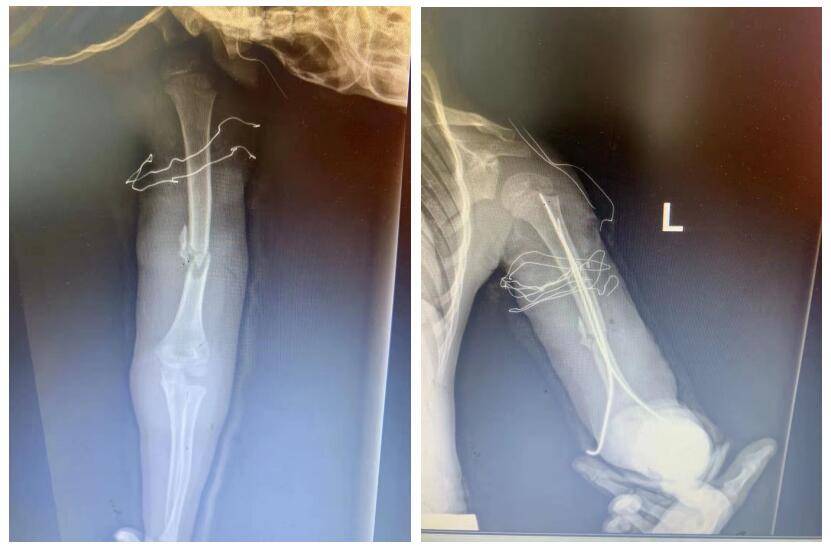

髌骨骨折空心钉联合钢丝固定一例

图片尺寸3120x4160